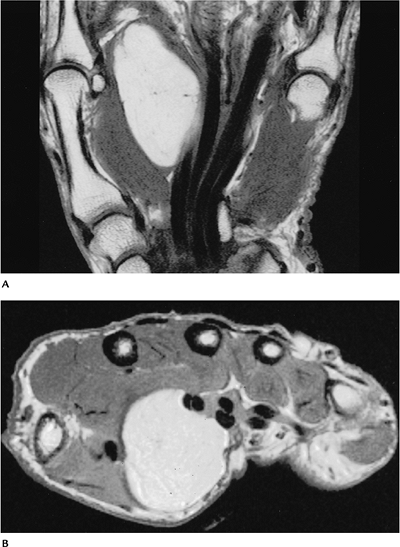

FIGURE 10-42 Benign lipoma. Coronal (A) and axial (B) T1-weighted MR images showing a well-defined mass of fat signal intensity along the flexor tendons of the hand.